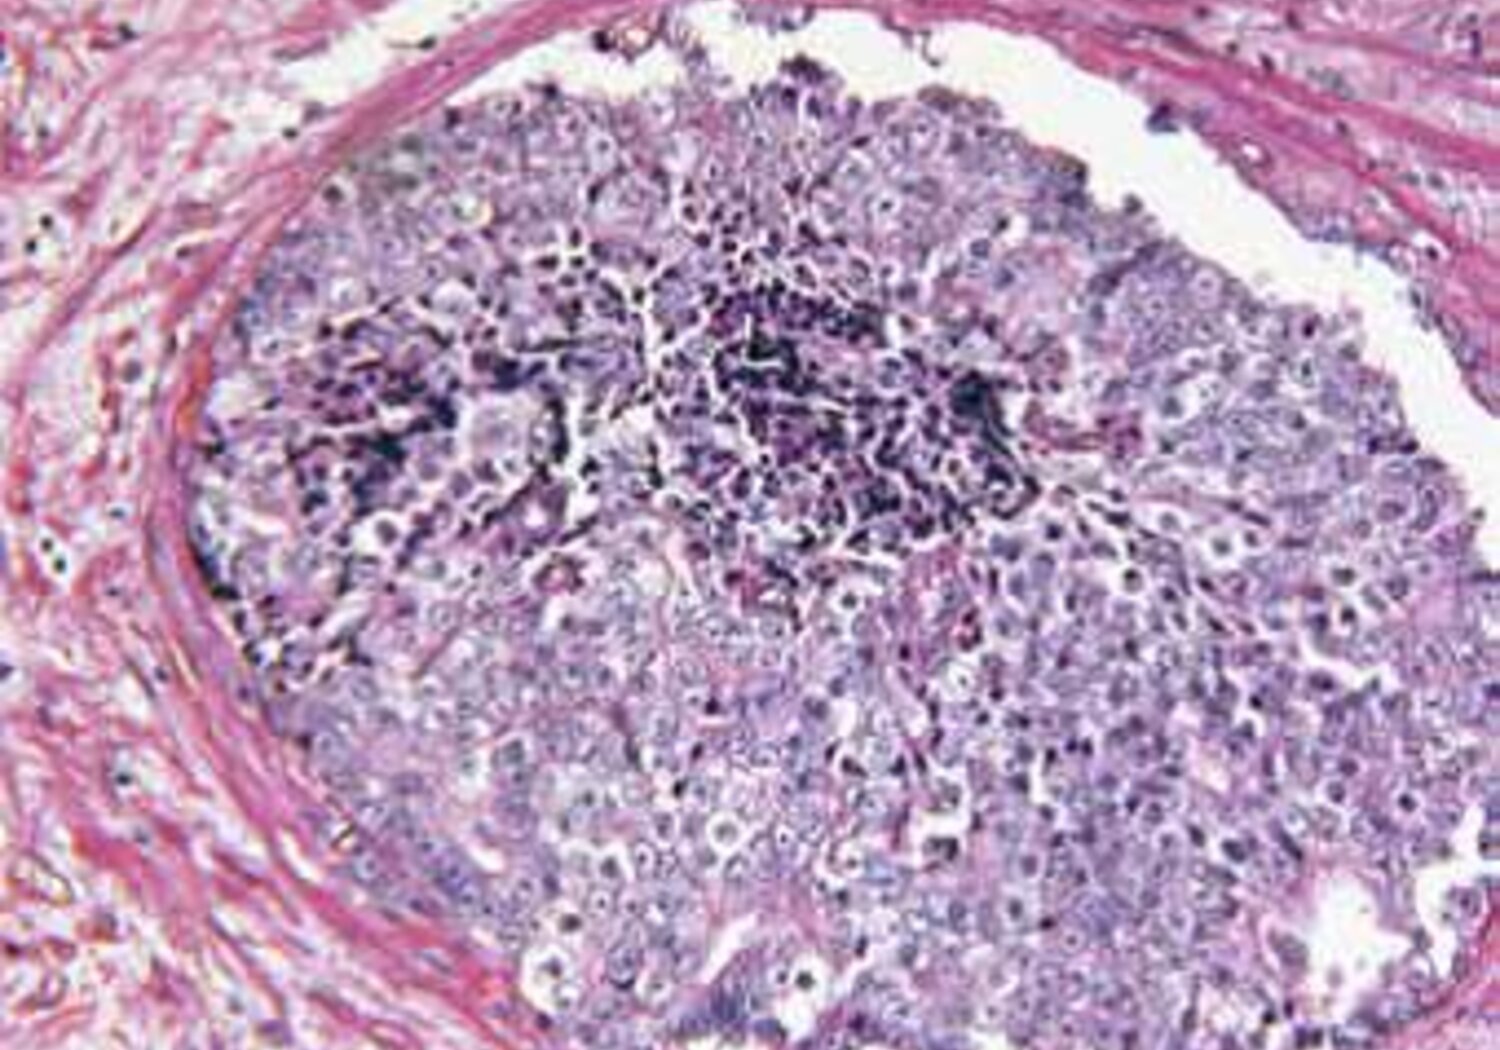

Prostate Gland Adenocarcinoma

Molecular radiotherapy (MRT) specifically targets cancerous cells through the use of radioactive treatments that attach themselves to tumours in specific parts of the body, such as the liver. Currently, molecular radiotherapy is used in palliative care but it has the potential to become a first line treatment for cancer. Tailoring MRT for individual patients relies on accurately measuring the radioactivity of the drug and determining the therapeutic dose delivered to the tumour.